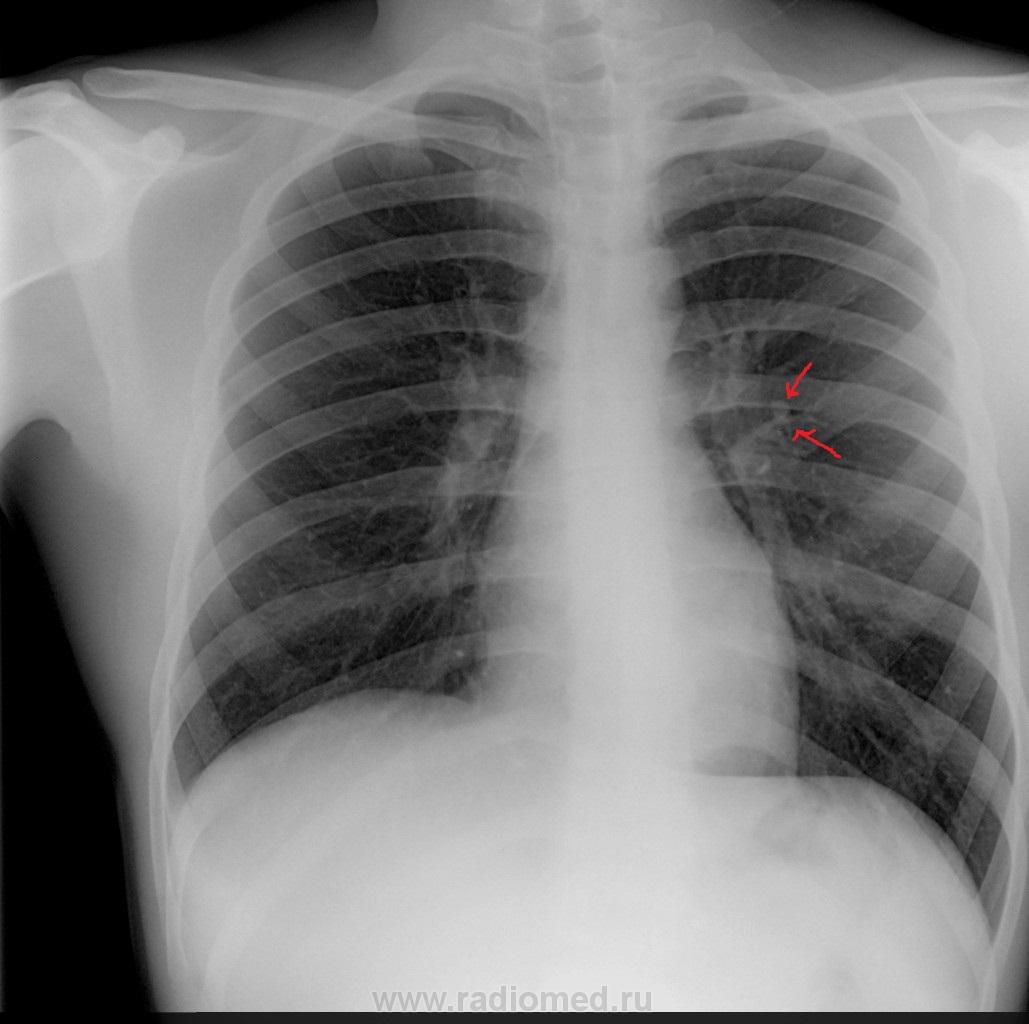

Пол пациента: Мужской пол Тип патологии: Другое Область исследования: Грудная клетка и верхние дыхательные пути Методы исследования: Rg Пациет 20 лет. Жалобы на боли в правой! половине грудной клетке. Объективно: болезненность при пальпации 6 и 7 межреберных промежутков справа!. Направлен на дообследование. https://radiomed.ru/sites/default/files/styles/case_slider_image/public/user/351/1992g.jpg?itok=8ubI0VCA ID:19584 Ср, 14/03/2012 - 11:33 #1 Кирилл Не на сайте Был на сайте: 6 лет 1 месяц назад Зарегистрирован: 11.09.2008 - 17:18 Публикации: 8 1Приложения: Кирилл Ср, 14/03/2012 - 10:28 #2 Побединский Мих... Не на сайте Был на сайте: 7 лет 9 месяцев назад Зарегистрирован: 25.12.2010 - 23:44 Публикации: 696 Тангенциальное сечение сосуда. Ср, 14/03/2012 - 10:35 #3 Viktoriya_K Не на сайте Был на сайте: 12 лет 8 месяцев назад Зарегистрирован: 19.10.2010 - 22:45 Публикации: 8 +1 Ср, 14/03/2012 - 11:09 #4 Helios Не на сайте Был на сайте: 7 месяцев 2 недели назад Зарегистрирован: 06.08.2010 - 15:16 Публикации: 4417 Скорее всего, сосуд. Как будете дообследовать? Ср, 14/03/2012 - 11:36 #5 Кирилл Не на сайте Был на сайте: 6 лет 1 месяц назад Зарегистрирован: 11.09.2008 - 17:18 Публикации: 8 дообследование и заключалось а в рентгене и ОАМ и ОАК ))) Кирилл Ср, 14/03/2012 - 11:38 #6 Кирилл Не на сайте Был на сайте: 6 лет 1 месяц назад Зарегистрирован: 11.09.2008 - 17:18 Публикации: 8 просто такое ощущение что "сидит"на сосуде образование Кирилл Ср, 14/03/2012 - 13:59 #7 stovbav Не на сайте Был на сайте: 2 года 2 месяцев назад Зарегистрирован: 20.12.2009 - 17:28 Публикации: 7066 Кирилл wrote: просто такое ощущение что "сидит"на сосуде образование Сделайте снимок с небольшим поворотом и на большем вдохе...вот тень и "разьедется")))) Болезни ног: виды, симптомы, причины, профилактика и лечение Ср, 14/03/2012 - 19:14 #8 Чижевский Вадим... Не на сайте Был на сайте: 3 года 3 недели назад Зарегистрирован: 12.11.2008 - 21:21 Публикации: 43 Посмотрите за экраном. Есть ли пульсация? Изменяет ли форму при поворотах? А если это ортопроекция сосуда, то и вопрос будет снят.

Тангенциальное сечение сосуда.

Скорее всего, сосуд. Как будете дообследовать?

просто такое ощущение что "сидит"на сосуде образование

Сделайте снимок с небольшим поворотом и на большем вдохе...вот тень и "разьедется"))))

Посмотрите за экраном. Есть ли пульсация? Изменяет ли форму при поворотах? А если это ортопроекция сосуда, то и вопрос будет снят.